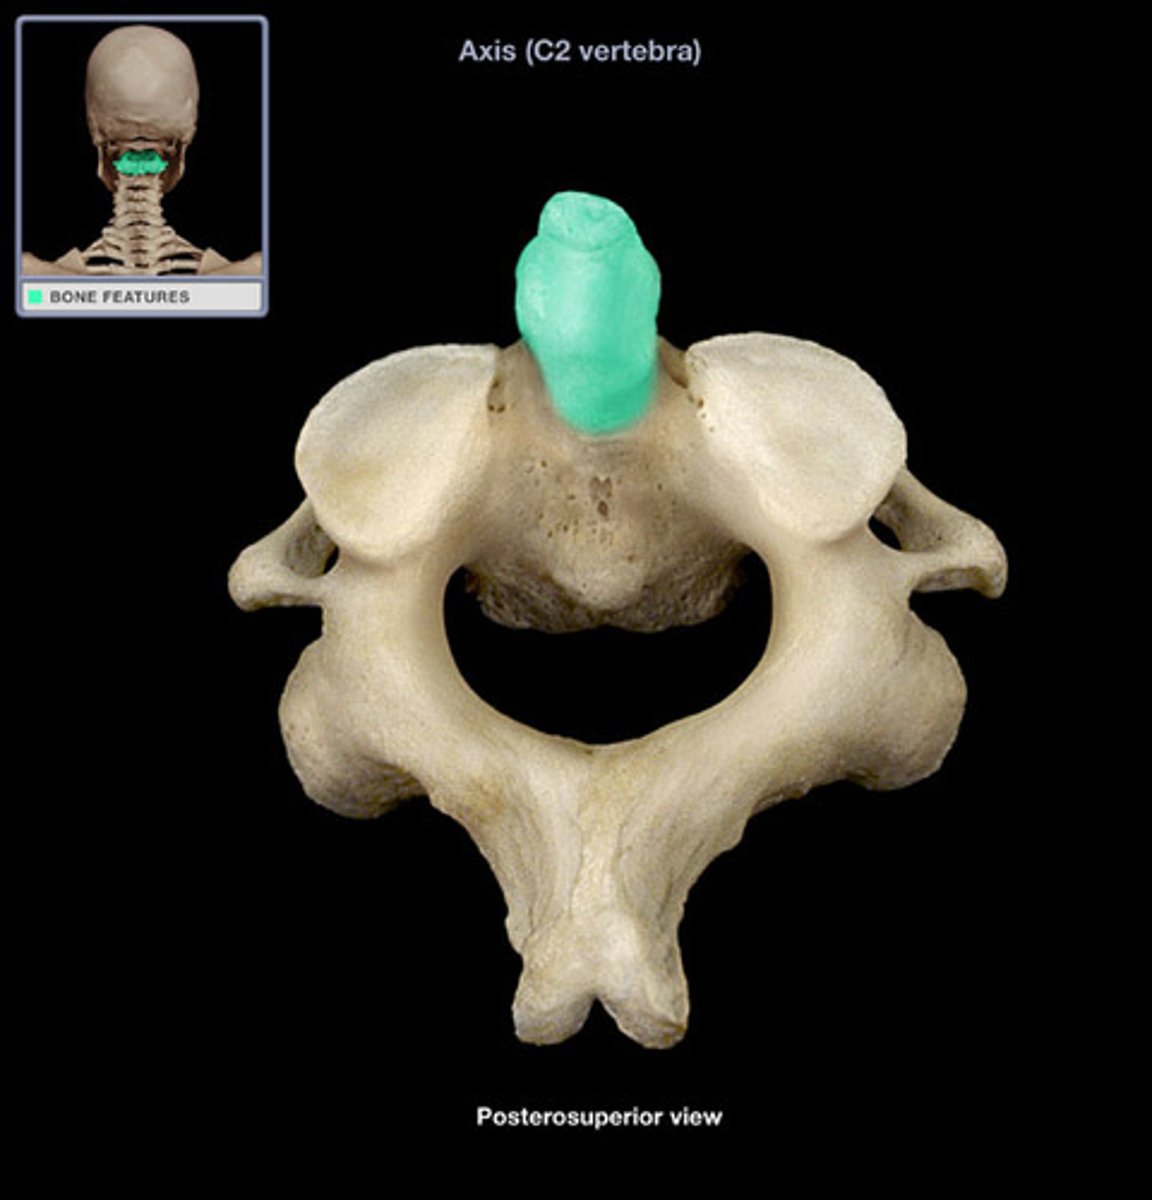

Axis

"no motion"

dens (odontoid process)